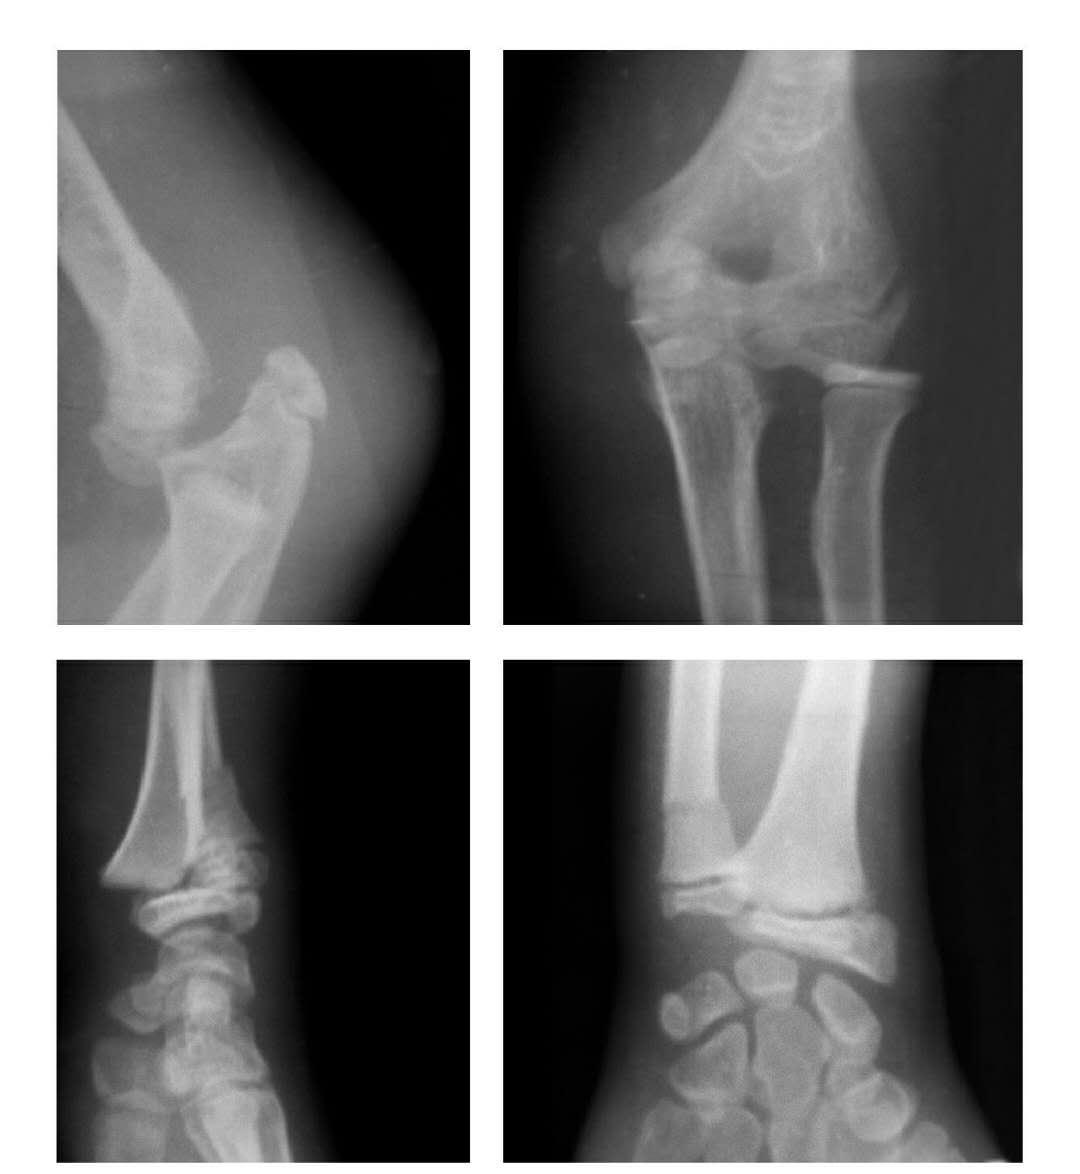

桡骨颈骨折(歪戴帽)

本病即桡骨小头骨折后关节面向外呈不同程度的倾斜。

例1:桡骨颈骨折后关节面向外倾斜50°。

例2:桡骨颈骨折后关节面向前外方呈130°倾斜移位。

桡骨头骨折

例1:桡骨小头前外侧缘骨折,骨块向肘前移位。

例2:桡骨小头矢状面骨折,折块呈上下翻转倒置分离。

例3:艾-鲁(Essex-Lopresti)二氏骨折并腕骨骨折:即桡骨头骨折,骨块移向肘前及同侧下尺桡关节脱位并腕经舟骨月骨周围性腕骨背侧脱位。